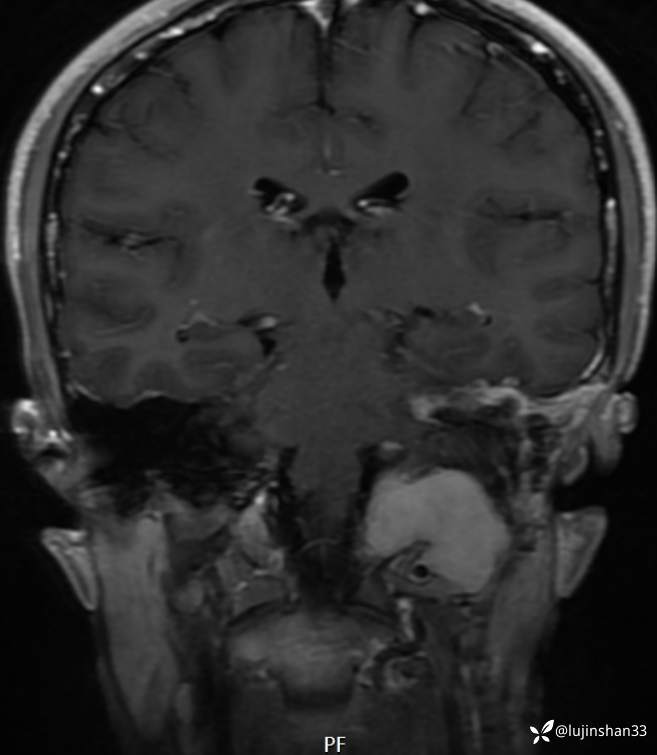

二次手术后1年半,肿瘤切除术后,未见复发

【治疗经过及结果】:左侧颞枕入路颞骨枕下骨巨细胞瘤切除,腹部脂肪填充